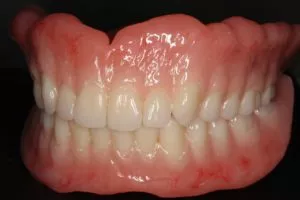

症例写真の紹介

ここで、当院がこれまでに治療してきたオールオン4やザイゴマの症例写真をご覧ください。お口の状況がどれほど改善されるかがイメージしやすくなるかと思います。

症例②オールオン4

• Before

• After

咀嚼、審美障害。歯周病でグラグラな歯を全部抜歯してオールオン4で治療した症例。